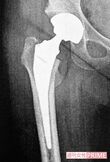

岡崎友紀さんの右脚に入っている人工股関節のエックス線画像

[写真 5/5枚目] 岡崎友紀さんの右脚に入っている人工股関節のエックス線画像